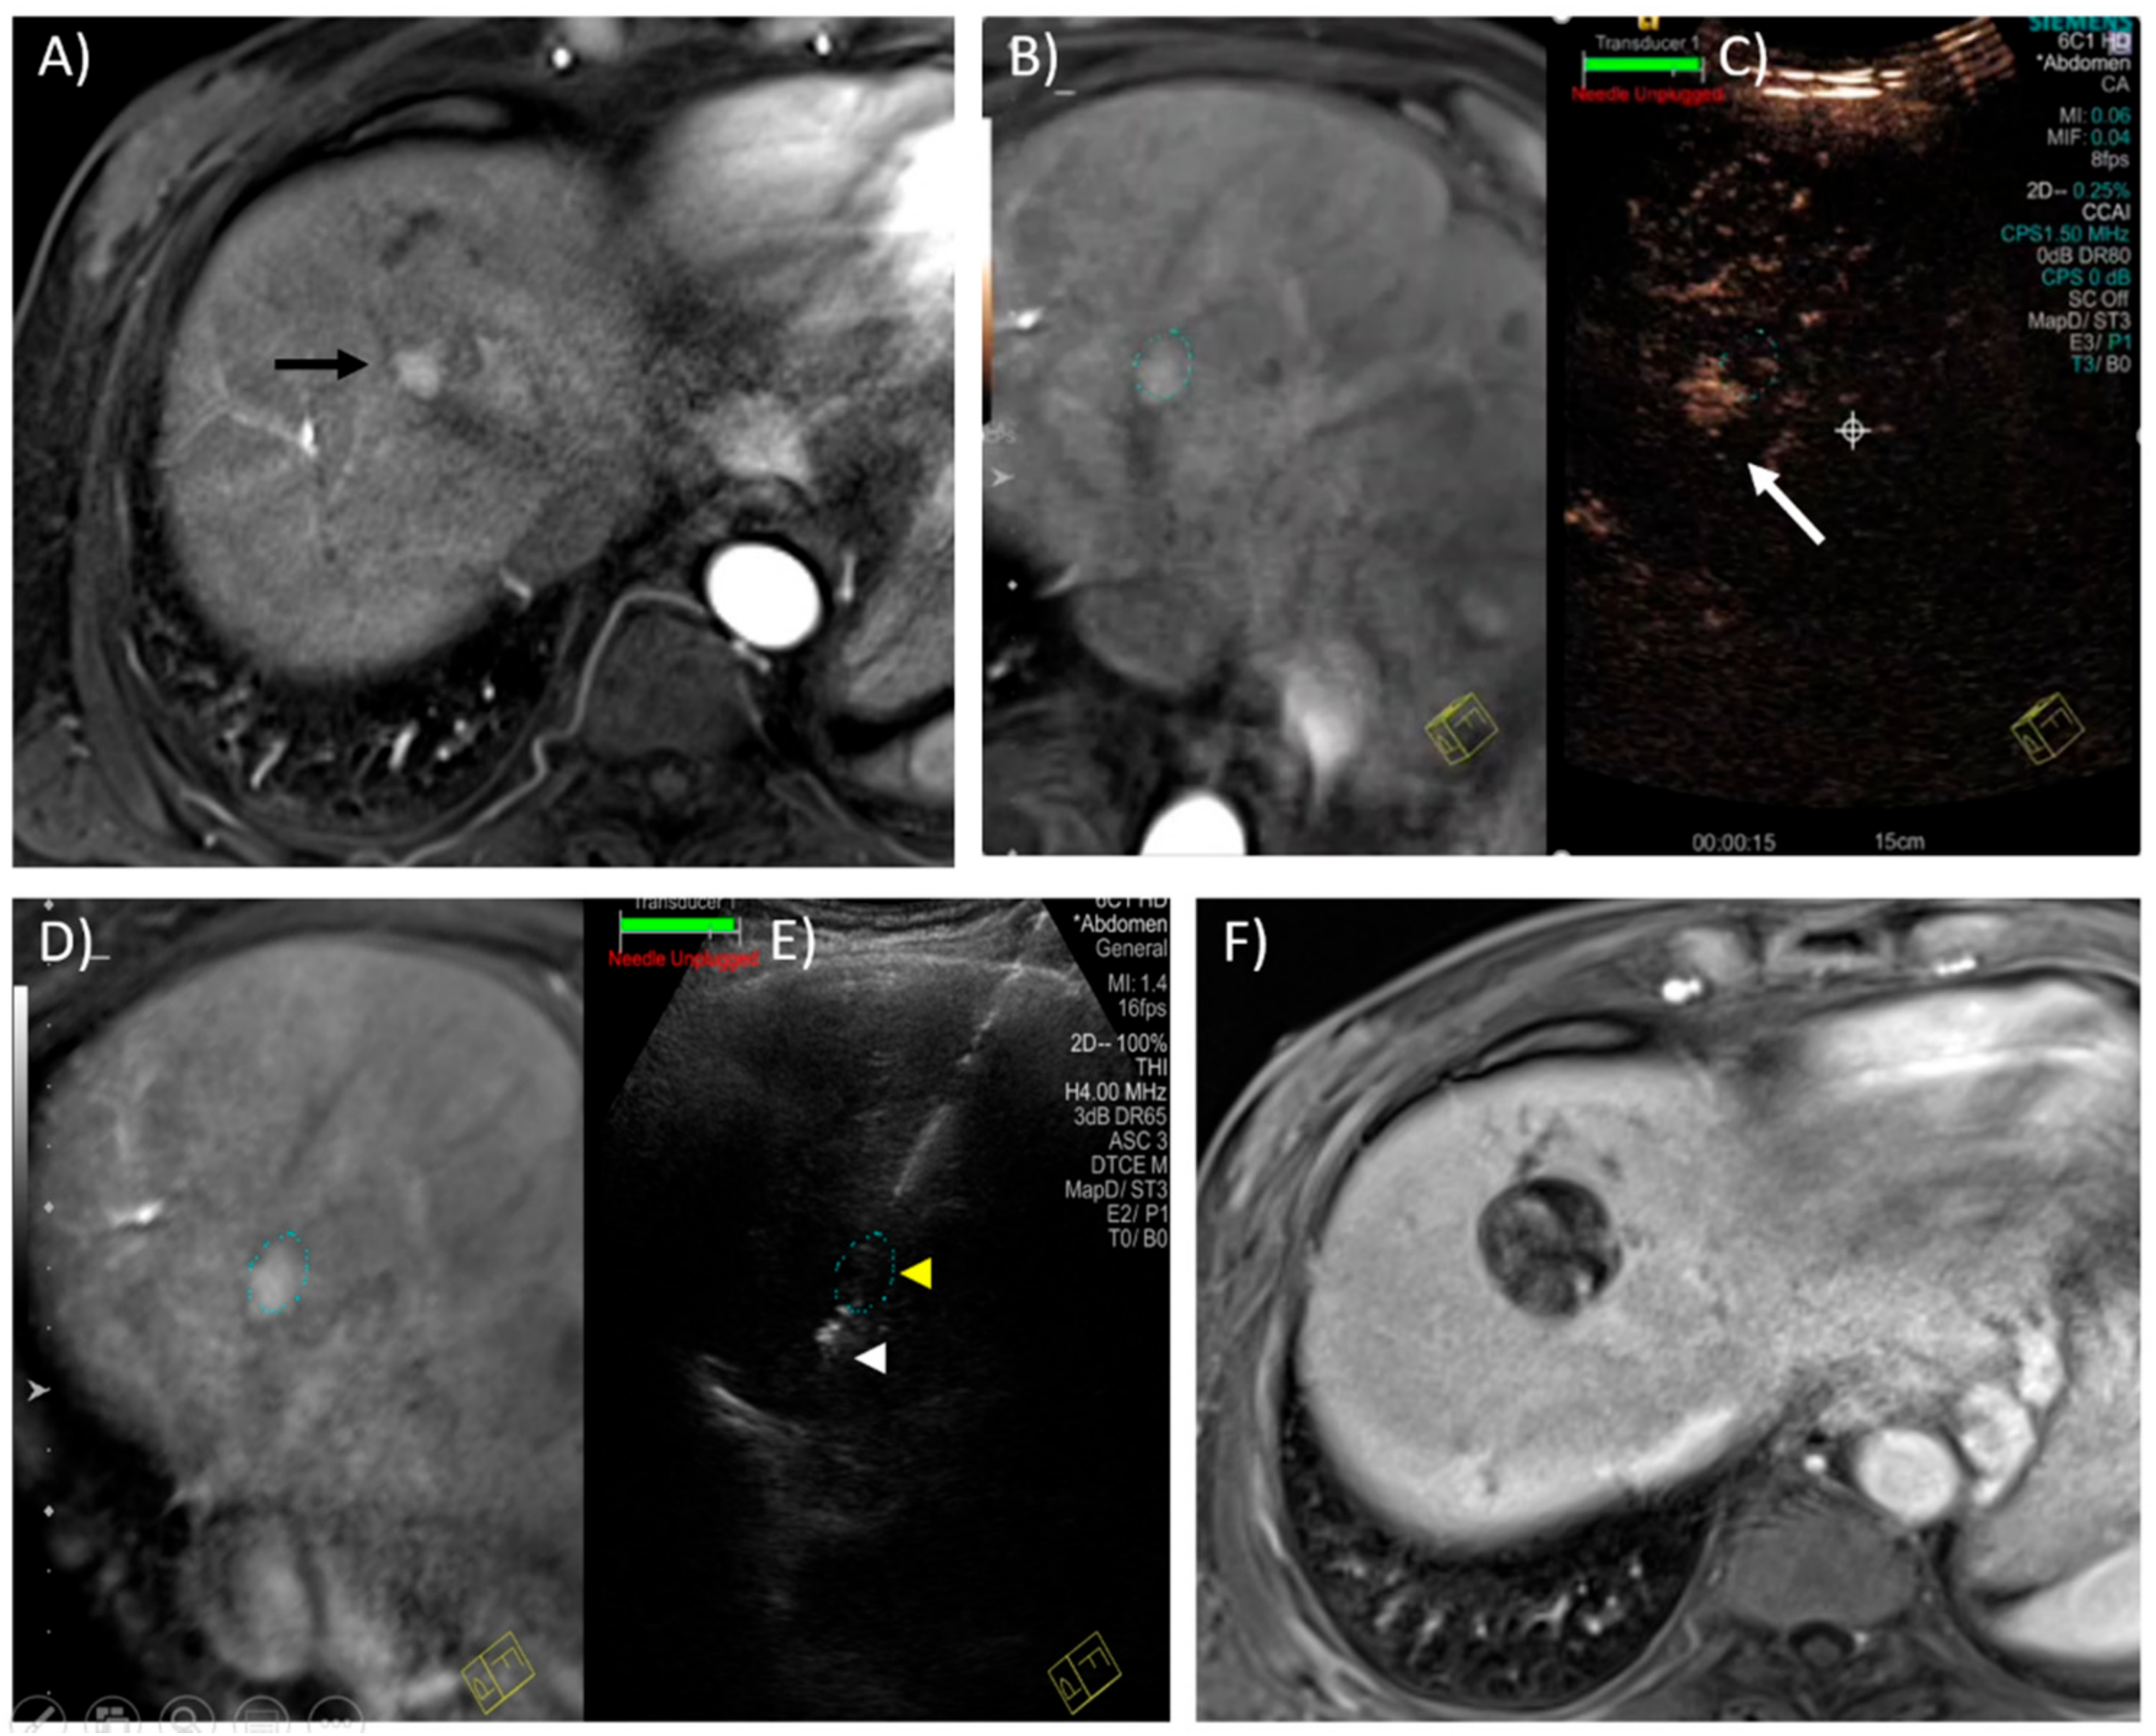

- Kim, T.K.; Khalili, K.; Jang, H.-J. Local ablation therapy with contrast-enhanced ultrasonography for hepatocellular carcinoma: A practical review. Ultrasonography 2015, 34, 235–245. [Google Scholar] [CrossRef] [PubMed][Green Version]

- Dong, Y.; Wang, W.-P.; Gan, Y.-H.; Huang, B.-J.; Ding, H. Radiofrequency ablation guided by contrast-enhanced ultrasound for hepatic malignancies: Preliminary results. Clin. Radiol. 2014, 69, 1129–1135. [Google Scholar] [CrossRef]

- Rajesh, S.; Mukund, A.; Arora, A.; Jain, D.; Sarin, S.K. Contrast-enhanced US-guided Radiofrequency Ablation of Hepatocellular Carcinoma. J. Vasc. Interv. Radiol. 2013, 24, 1235–1240. [Google Scholar] [CrossRef]

- Park, H.S.; Kim, Y.J.; Yu, M.H.; Jung, S.I.; Jeon, H.J. Real-time contrast-enhanced sonographically guided biopsy or radiofrequency ablation of focal liver lesions using perflurobutane microbubbles (sonazoid): Value of Kupffer-phase imaging. J. Ultrasound Med. 2015, 34, 411–421. [Google Scholar] [CrossRef]

- Lee, J.Y.; Minami, Y.; Choi, B.I.; Lee, W.J.; Chou, Y.H.; Jeong, W.K. The AFSUMB Consensus Statements and Recommendations for the Clinical Practice of Contrast-Enhanced Ultrasound using Sonazoid. Ultrasonography 2020, 39, 191–220. [Google Scholar] [CrossRef]